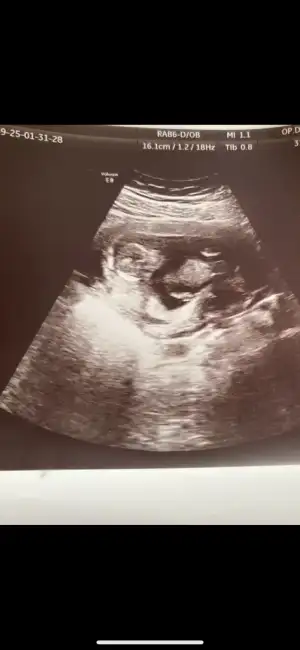

Buda 12+2 haftalık hala aynı fikirde misiniz acaba?Bence erkek sizin![]()

Bilmem ben öyle hissettim ama doktor daha iyisini bilir tabikiBuda 12+2 haftalık hala aynı fikirde misiniz acaba?

öğrendiniz mi deniz hanımBuda 12+2 haftalık hala aynı fikirde misiniz acaba?